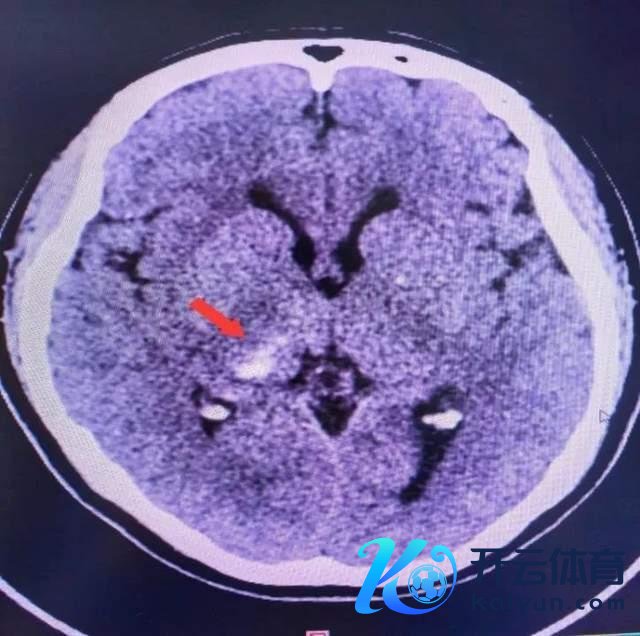

接诊的是脑血管神经外科主任医生刘坤,流程详备查验,发现梁女士脑袋内部果真出血了……万幸的是梁女士颅内出血量未几。入院时刻经雅致颐养,摒除其它高危成分,加上脑心健康不休师全程不休及布道,经复查浮现颅内出血基本接纳,梁女士痊可顺利出院。